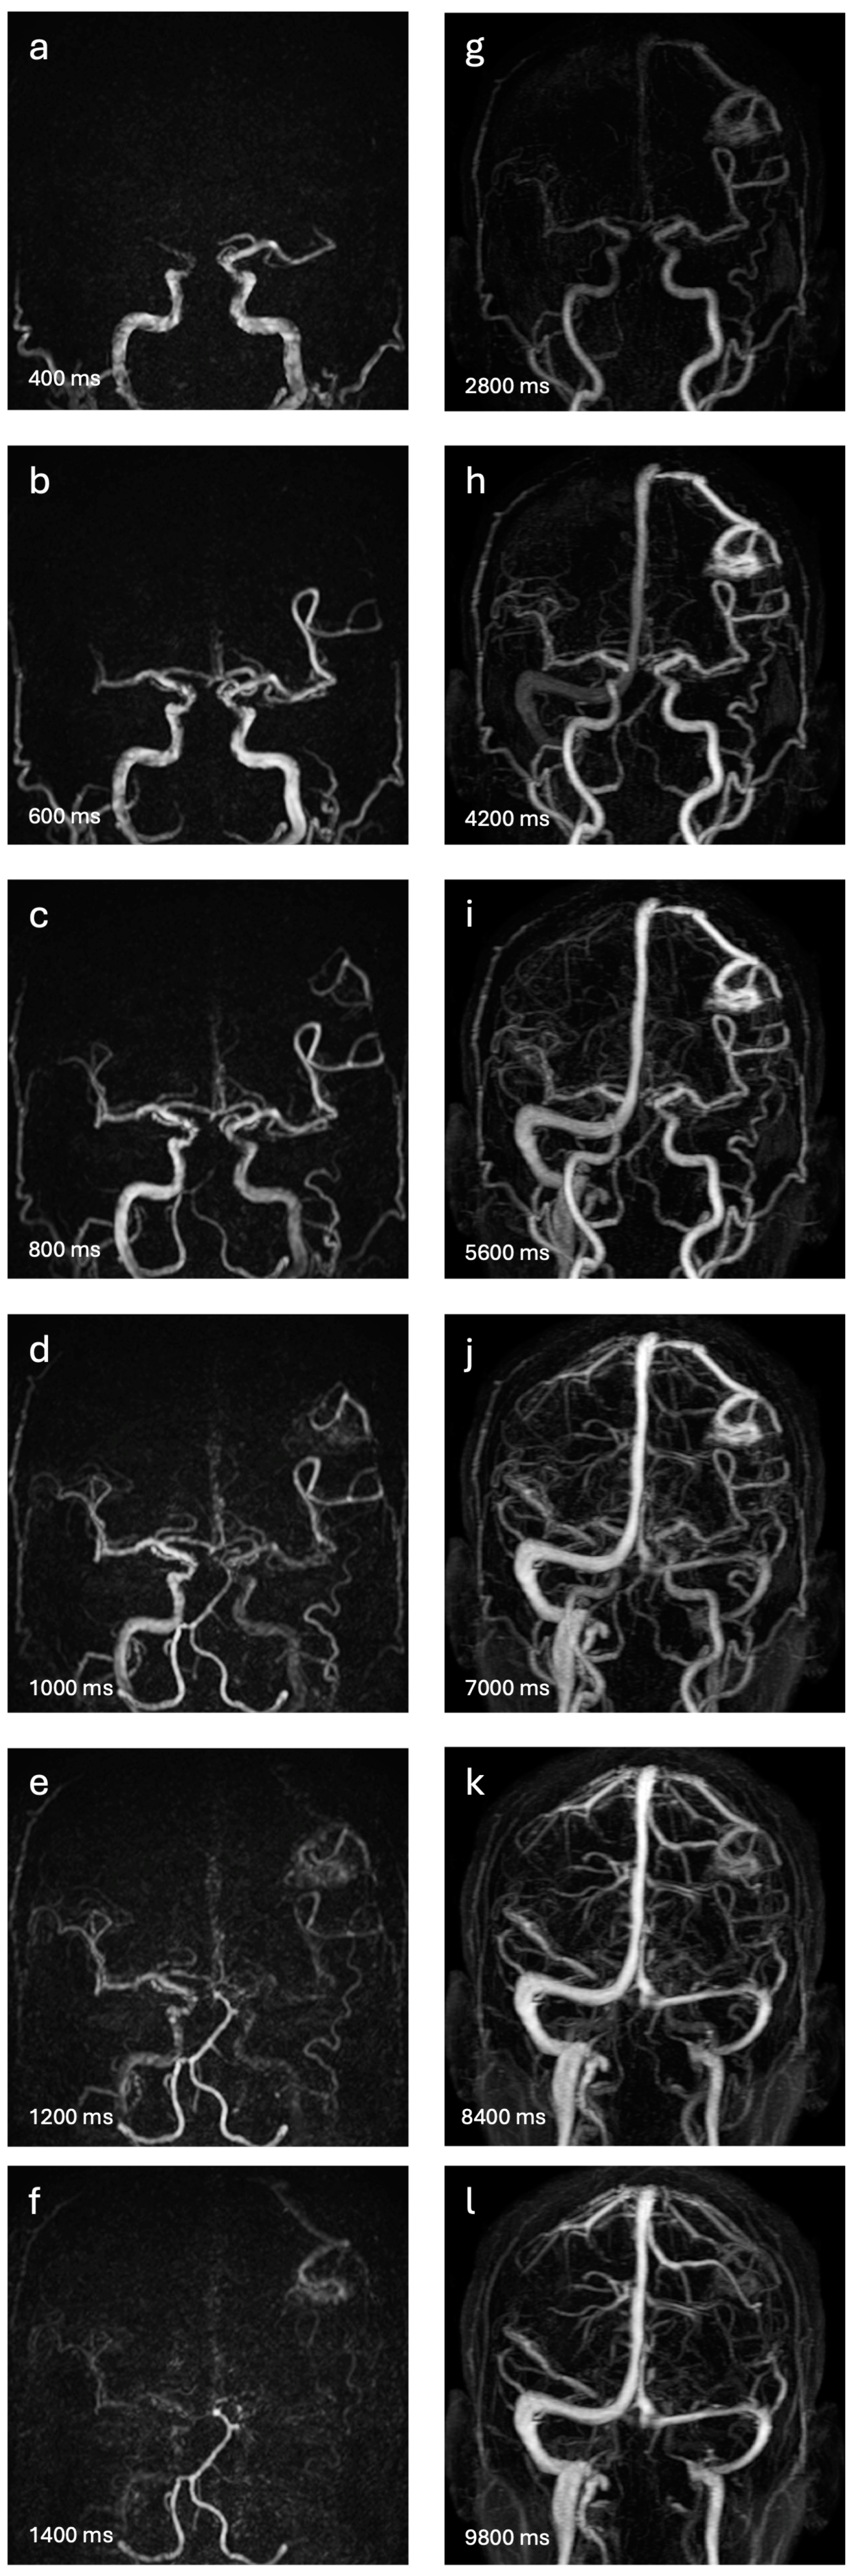

2.2. Four-Dimensional MRA Techniques